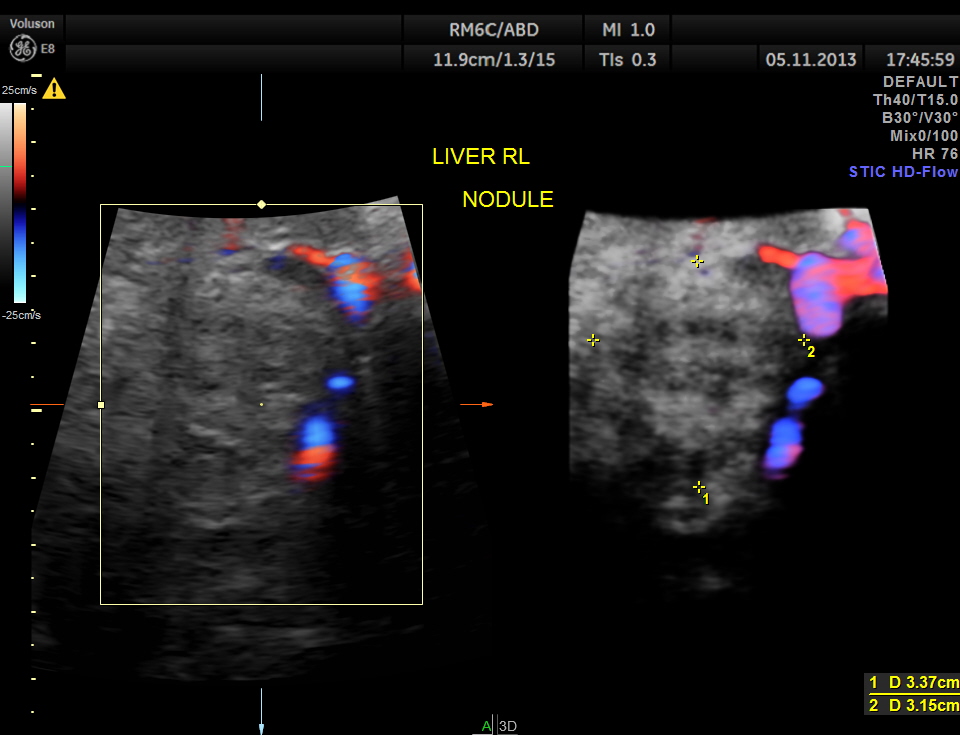

Glass body reconstruction of a right lobe liver nodule ,

This patient had a painful metastatic nodule in the right lobe of the liver. He also had loculated sub diaphragmatic collection and a septated cystic mass in the free surface of the liver.